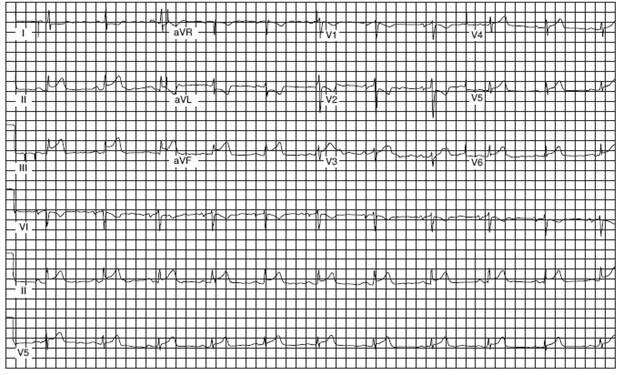

A 54-year-old man presents to the emergency department complaining of epigastric discomfort, which began while he was walking his dog after dinner about one-half hour earlier. He has not received medical care for several years. On examination, he is moderately obese and in obvious discomfort and seems restless. His BP is 160/98 mmHg, and his examination is otherwise unremarkable. His ECG is seen in Figure below:

Which of the following is the most likely diagnosis?

Answer(s): D

This ECG reveals ST-segment elevation in II, III, and AVF, indicating acute injury of the inferior wall of the myocardium. Inferior wall ischemia can be perceived as pain in the epigastric area. Anterolateral myocardial infarction would show loss of R-wave progression in V4 through V6. Pericarditis would show diffuse ST segment elevation in limb and precordial leads. Although his symptoms could suggest gastroesophageal reflux, this ECG shows this a cardiac event. Costochondritis is not present by examination. When ST segment elevation is present, a patient should be considered a candidate for reperfusion therapy or primary percutaneous intervention (PCI) such as angioplasty and stenting.

If no contraindications are present and PCI is unavaliable, thrombolytic therapy should ideally be initiated within 30 minutes, right in the emergency department. The goal of both thrombolysis and PCI is prompt restoration of coronary arterial patency. Thrombolytic therapy can reduce the risk of in- hospital death by up to 50% when administered within the first hour of symptoms, so time is of the essence. Arranging for a bed may waste time for limiting infarct size. The ECG would obviously preclude the other two options:

immediate trial of antacid or reassurance and arranging outpatient follow-up.